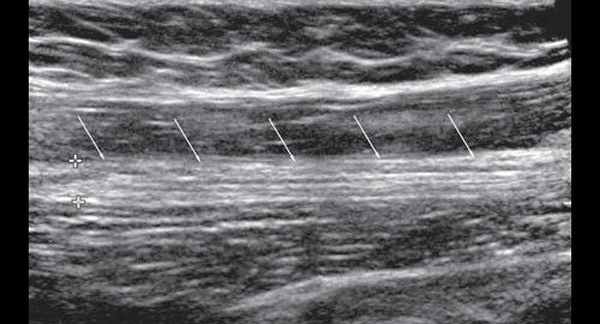

УЗИ бедренного нерва проводили в положении пациента лежа на спине. Бедренный нерв визуализировали в паховой области латеральнее сосудистого пучка от уровня паховой связки до верхней трети бедра (рис. 2, 3). Исследование проводили в поперечной и продольной плоскостях сканирования (рис. 2, 4).

Рис. 4. В-режим. Исследование правого бедренного нерва в продольной плоскости сканирования на уровне паховой области и верхней трети бедра: стрелки - бедренный нерв.